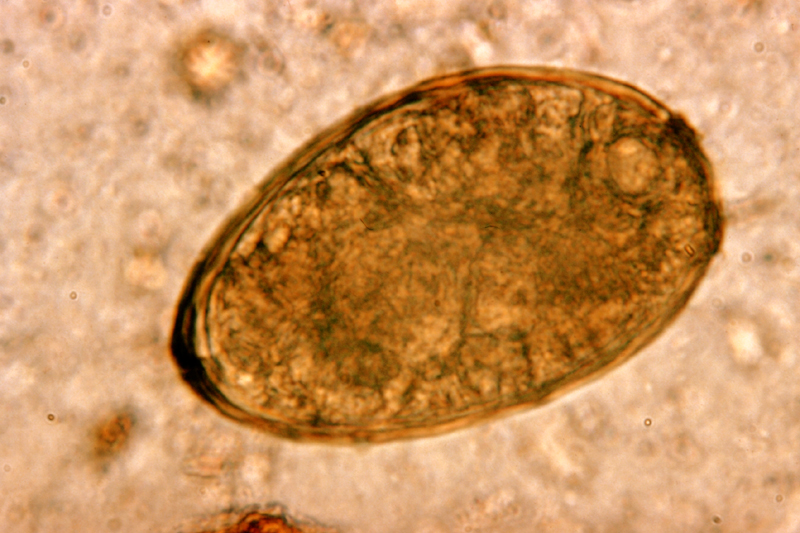

Parasieten had hij ook. In zijn darmen vond men een lintworm en lintwormeieren en in zijn spierweefsel eieren van spoelwormen, die afkomstig zijn uit rauw varkensvlees en trichinellose veroorzaken.

Nacht moet erg veel met verontreinigd water in aanraking gekomen zijn, want in zijn blaas, lever en nieren bevonden zich zuigwormen, overbrengers van de bilharzia.

Deze aquatische wormen dringen door de huid het menselijk lichaam binnen, belanden via het lymfestelsel in de lever, waar ze zich verder ontwikkelen om zich vervolgens over het hele lichaam te verspreiden. Daarnaast leed onze patiënt waarschijnlijk ook aan levercirrose.

Tekens van aandoeningen zoals schistomiasis of bilharziasis (parasitaire aandoening van vooral hier van de urineblaas, maar ook van de darmen) en ook ankylostomiasis (de mijnworm die bloedingen van de twaalfvingerige darm en dunne darm veroorzaakt) zijn teruggevonden bij mummies.

♦♦ Darmparasieten ♦

- Taenia solium (lintworm)

- Trichinella